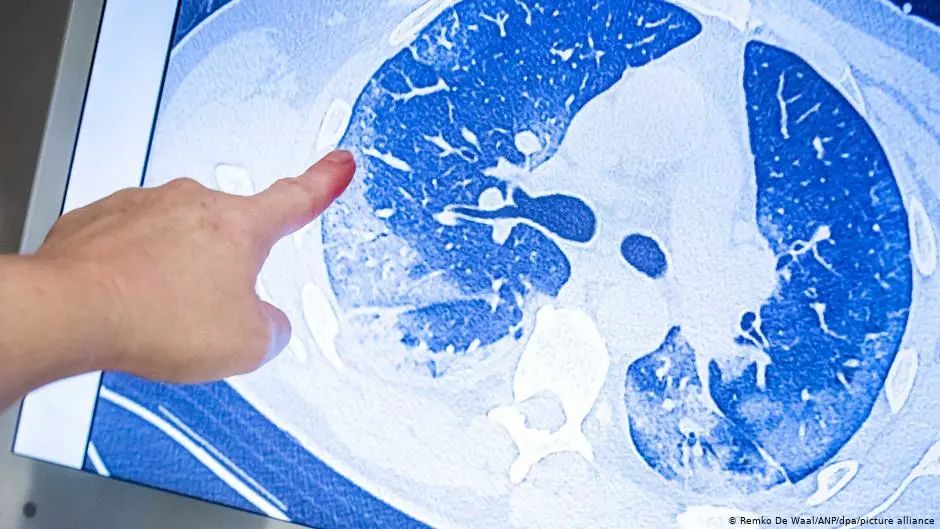

随着COVID-19大流行病在全球范围内的持续存在 , 医学上新出现的挑战是从应对急性感染转向应对新冠长期后果对医疗体系造成的负担 。 全球据估计有近10%左右的新冠康复者患有不同的新冠后遗症 , 据国家卫健委官方网站8月31日数据 , 国内累计报告确诊病例94879例 , 死亡病例4636例 。 治愈出院病例89145例 。 这89145例确诊治愈出院病例中有多少人患有新冠后遗症 , 他们的康复情况如何?这些新冠后遗症有那些症状?8月28日 , 国际著名医学杂志《柳叶刀》上发布了一项关于国内新冠患者后遗症的新研究 。 这是目前最大型的、时间长达一年的随访 , 评估了2020年初曾在武汉金银潭医院住院的1276名新冠病人 , 在出院后12个月的健康状况 , 对国内新冠后遗症患者的情况 , 提供了最新的数据 。 这篇论文显示 , 这1276名新冠患者出院出院12个月后 , 仍有:—30%呼吸困难—26%抑郁/焦虑—12%没有回到病前的工作 。 国外新冠后遗症的症状共有205个 , 中国共有多少个?这篇论文显示:肌无力/疲倦、抑郁/焦虑、呼吸困难、睡眠困难、脱发、关节痛等 , 是目前为止随访患者较为主流的后遗症 。 新冠病后的疲劳或肌无力看上去无足轻重 , 实际上它是慢性的长期的疲倦 , 不少人还有劳累后不适的现象 , 即体力或者脑力消耗后症状会恶化 , 严重影响患者的生活 , 有的人因此不能工作、或不敢出门 。 另据这篇研究文章的相关数据 , 如果把排除的56位有精神问题/痴呆症而不能参加随访的患者也部分考虑在内的话 , 那有精神症状的人群比例其实更高 。